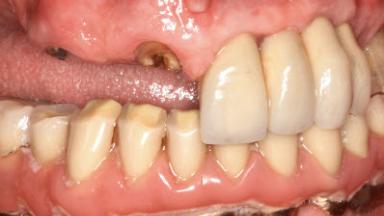

Retreatment of a Patient with Multiple Biological and Technical Complications and Failures

A 66-year-old patient presented because of retention loss of the tooth-supported FDP in the right maxilla (x-13-x-11). The mandibular full-arch implant-supported reconstruction (x-i34-i33-x-x-x-x-i43-i44-x) had suffered extreme wear. His medical history revealed high blood pressure, controlled with anti-hypertensive medication. The patient was a light smoker (2 to 3 cigarettes per day). The existing reconstructions had been performed alio loco about five years previously. That treatment had taken an extensive amount of time, and as early as during the fabrication of the reconstructions, multiple complications had occurred with the provisionals.

SAC Level Complex

Defining Characteristics Fully edentulous upper jaw to be rehabilitated with an implant-borne removable overdenture